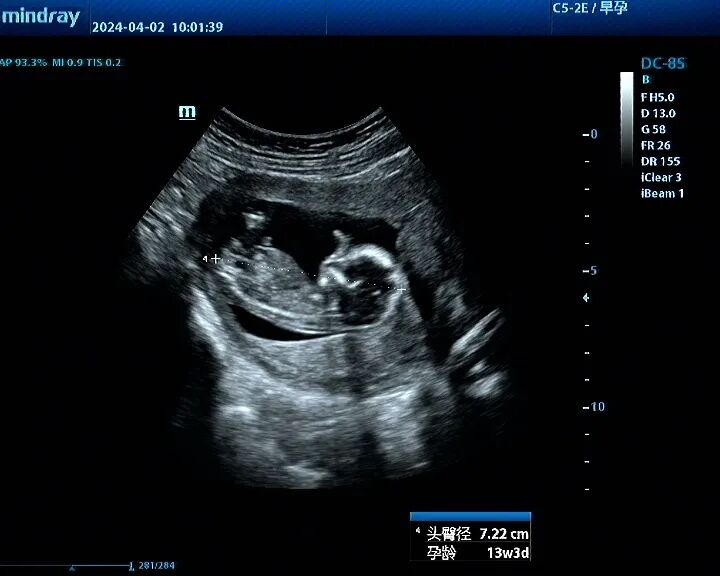

第六次宫腔镜:2024年2月自然妊娠10周,2024年4月初妊娠3+月(BPD2.6cm),坚决要求终止妊娠,行宫腔镜辅助终止妊娠。门诊医生给与米非司酮片及米索前列醇口服3天,胚胎掉出后行宫腔镜辅助下清宫,确保无胚物残留,术前宫深11.5cm,术后宫深10cm。